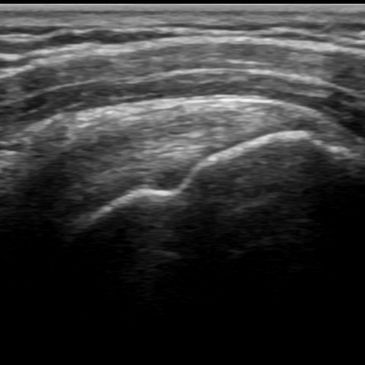

Ultrasound Scanning Guide for Abdomen and Male Pelvis

Ultrasound Scanning Guide for Obstetrics and Gynecology

Published by Wiley